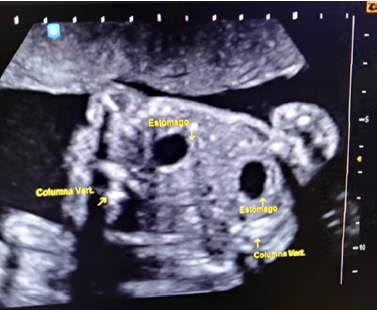

Se trata de paciente femenina de 19 años, sin antecedentes familiares, personales y patológicos conocidos, IV gestas, II cesáreas, I aborto, FUR 18/08/2018, quien acude a especialista en medicina materno-fetal y en vista de hallazgos ecográficos es referida a la Unidad de Perinatología y Medicina Materno-Fetal del Hospital Materno Infantil Dr. José María Vargas, siendo evaluada el 13 de febrero de 2019, donde se realiza estudio ultrasonográfico Perinatal en tiempo real, con transductor convex de 3,5 mHz, ecógrafo marca Esaote, visualizándose estructuras fetales compatibles con dos fetos que correspondían a un embarazo múltiple doble, se identificaron ambos polos cefálicos ubicados en el mismo plano de corte durante la exploración (Figura 1), 4 extremidades superiores, tórax y abdomen de ambos fetos fusionados, corazon único (Figura 2), de difícil evaluacion, impresionando defecto septal ventricular de 4,6 mm (Figura 3), 2 cámaras gástricas (Figura 4), 2 vejigas, sexo femenino, 4 extremidades inferiores, una sola placenta anterior, grado I, grosor 42 mm, con índice de líquido amniótico (ILA) máximo bolsillo vertical (MBV) de 43 mm. Concluyéndose estudio ecográfico con diagnósticos de: Embarazo múltiple doble monocorial monoamniotico (Duplicata completa: siameses toracoonfalopago) de 25 semanas más 4 días por fecha de ultima menstruación con corazon único asociado a posible comunicación interventricular (CIV) sub-aortica.